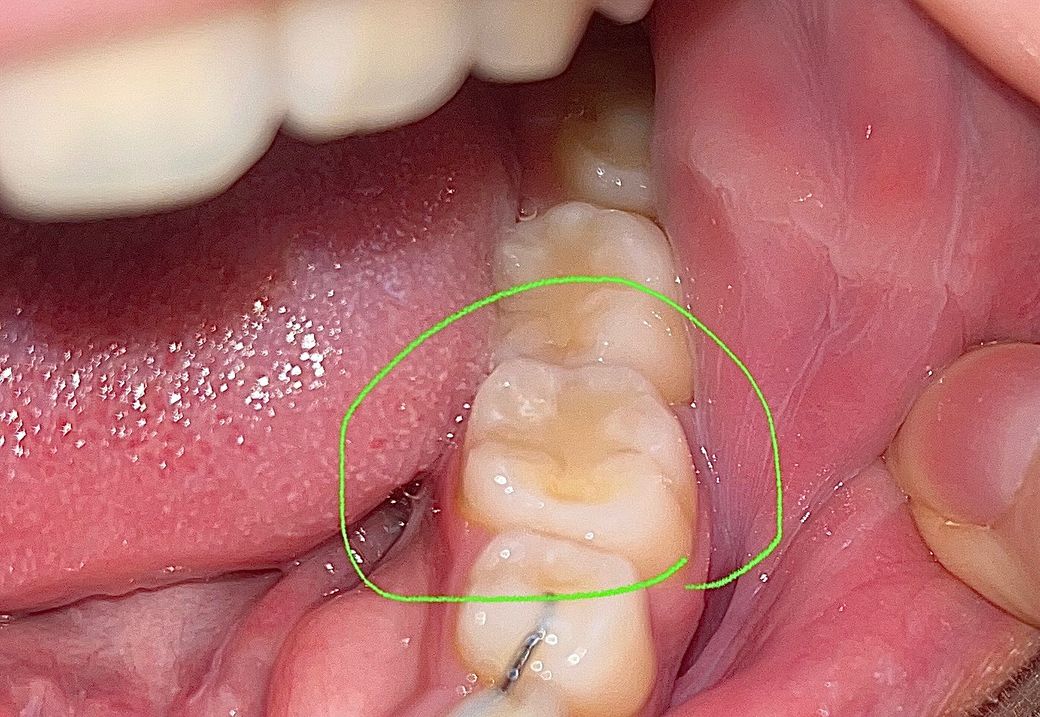

레진 치료 한지 2개월 정도 되었고 치료 전에는 전혀 통증이나 시림은 없었습니다. 치료 직후부터 지금까지 딱딱한 음식, 신 음식 먹을 때 찌릿하게 시립니다. 평소에는 양치할 때 아무 반응 없다가 신거 먹고 양치하면 특히나 시립니다 ㅠㅠ 찬물 뜨거운물에는 반응 없습니다.

사진에 레진 상태도 봐주세요.

사진으로 보였을 경우 레지는 잘 충전되어 있는 것으로 보입니다. 레진으로 충전한 부위가 불편감이 있거나 시린 느낌이 있다면 교합 간섭 등이 있을 수 있으며 레진의 접착이 잘 되지 않은 경우에도 해당 증상이 생길 수 있습니다.

사진상으론 레진이 별 문제없이 수복된 것으로 보이나 실제 검사는 해봐야압니다.